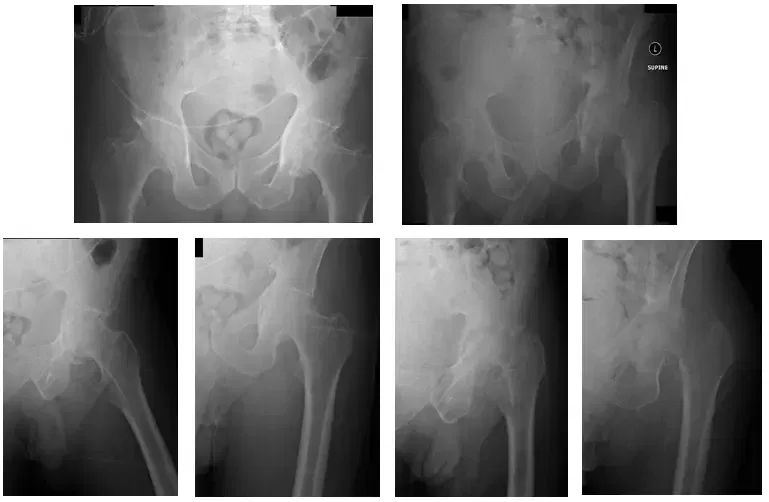

El paciente es un varón de 55 años que acudió quejándose de dolor bilateral en la cadera que, según declaró, había ido en aumento durante los últimos meses. El paciente acudió con radiografías para revisar, que indicaban que tenía artritis bilateral de las articulaciones de la cadera. A continuación se muestran las radiografías.

Las radiografías muestran artritis bilateral de la cadera con peores hallazgos de artritis en la articulación de la cadera izquierda.

Las radiografías también muestran un cambio erosivo severo de la cadera izquierda y una fractura basicervical en el cuello femoral. También se muestra una leve migración axial de la cabeza femoral de la cadera derecha.